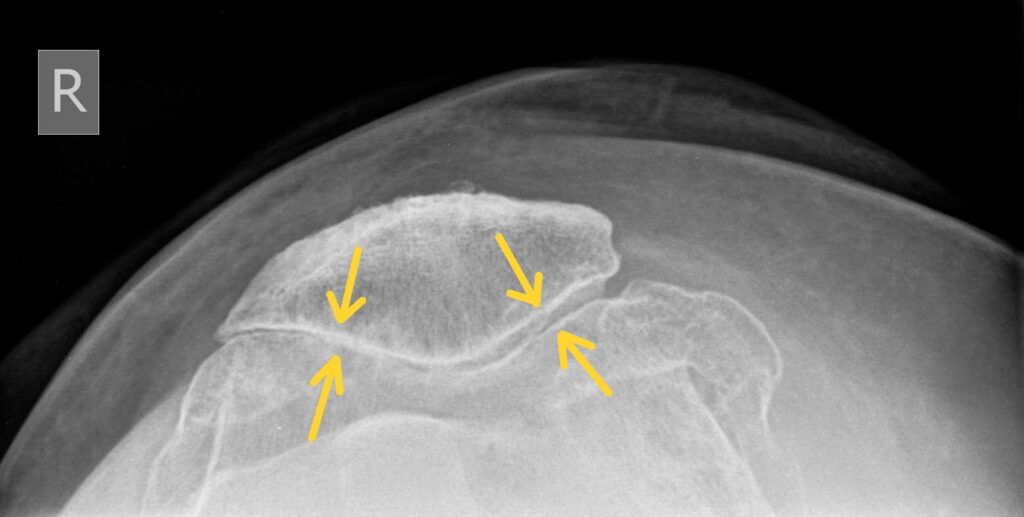

Retropatelläres (patellofemorales) Syndrom: Diese Form betrifft das Gelenk zwischen Kniescheibe und Oberschenkelknochen. Betroffene leiden besonders beim Treppensteigen und längerem Sitzen unter Beschwerden.

Röntgenbild einer schwerwiegenden Arthrose im Kniegelenk mit nahezu aufgebrauchten Gelenkspalt innen- und außenseitig (Pangonarthrose)